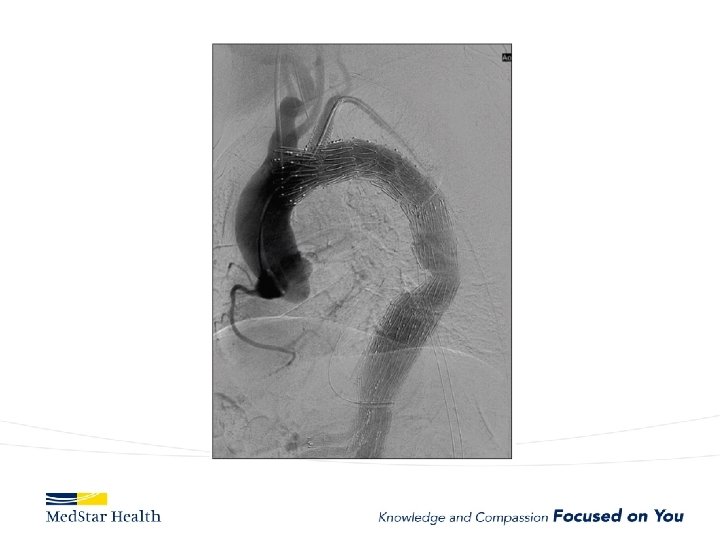

How Do We Treat • Open repair-unacceptable morbidity and mortality • TEVAR – Improved morbidity and mortality – Coverage of primary entry tear – Additional coverage?

Type B Dissection Complicated Uncomplicated Risk TEVAR age, comorbidities Extreme Low Medical Management False Lumen Small, Thrombosed Medical Management Patent/Large(>22 mm), Total Aorta >40 mm TEVAR/adjuncts